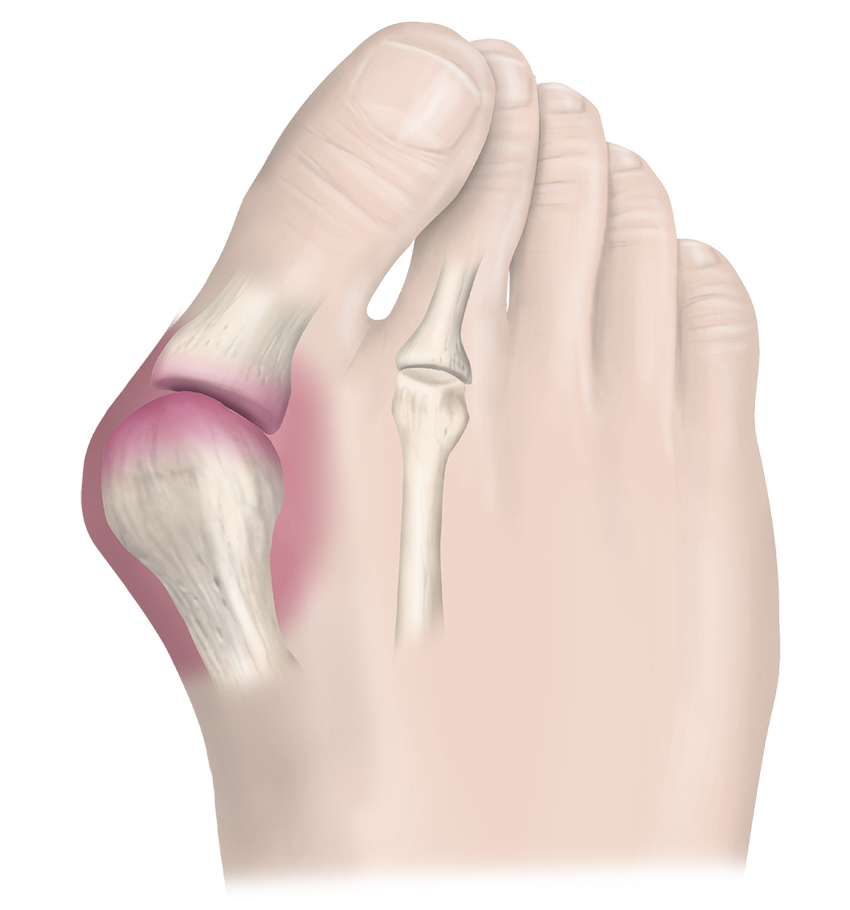

Hallux valgus karakteriseras av en felställning i metatarsofalangealled I, som kan bidra till smärta och estetiska besvär för patienten. Inte sällan påverkar felställningen valet av sko (svårt att hitta en passande sko) och gångstil.